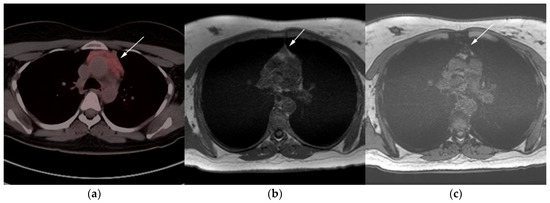

Figure 6.

Imaging in a different patient with known diagnosis of primary mediastinal B-cell lymphoma. (a) Axial FDG PET/CT images show the hypermetabolic anterior mediastinal mass (white arrows), and there is also central areas of absent metabolic activity within the mass (red arrow), correlating with areas of fibrosis, a finding that is essential in prebiopsy planning to avoid false negative results. (b) Axial FDG PET/CT images show hypermetabolic right upper paratracheal nodes (white arrows) and several additional hypermetabolic pulmonary and pleural-based nodules within right upper lung (red arrows). (c) H&E section shows that the tumor is composed of large, atypical cells with reniform or multi-lobulated nuclei with abundant clear cytoplasm. Note the lymphoma cells are compartmentalized by the prominent sclerotic bands of fibrosis. (Original magnification 400x, H&E stain).

Figure 7.

Imaging in a 20-year-old female with history of classic Hodgkin’s lymphoma (CHL) who had 4 cycles of chemotherapy. (a) Axial 18F-FDG PET/CT showing residual wedge-shaped/triangular activity seen within the anterior mediastinum (arrow). There was concern for residual disease vs. thymic rebound hyperplasia. (b) MRI axial T1 in phase and (c) MRI axial T1 out of phase show intermedial signal on T1 in phase (arrow) with dropped signal on the out of phase sequence (arrow), consistent with fat content due to thymic rebound hyperplasia.

Figure 8.

Imaging in a 60-year-old female presenting with ill-defined anterior mediastinal mass. (a) Axial 18F-FDG PET/CT showing ill-defined hypermetabolic mass within the anterior mediastinum (arrow). This was biopsy-proven thymic carcinoma. (b) MRI T1 in phase sequence, (c) MRI T1 out of phase—note there is no dropped signal on the T1 out of phase (arrows) due to lack of fat. This is consistent with residual disease.